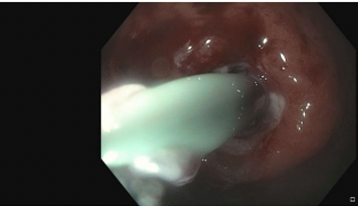

Images from personal library of Katelyn Cookson

Figure 2. Gastric Body, pus draining from gastric defect